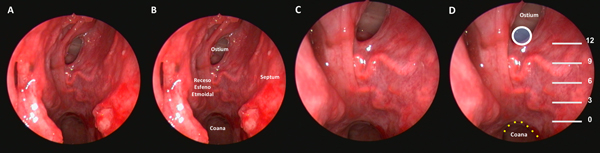

El próximo paso es identificar el ostium esfenoidal del lado derecho. Si el mismo no es visible, la maniobra más recomendada para identificarlo es utilizar un disector de Cottle para lateralizar el cornete superior en la unión de su tercio medio y posterior. Si aun así no logra identificarse, se procede palpando sin presionar demasiado en esta región hasta identificar una zona débil fenestrando delicadamente la mucosa. Se realiza finalmente un movimiento rotacional con el disector para ampliarlo (Figura 2 A-B).

La zona más baja del ostium coindice con el “punto de Cappabianca”, 12 mm por arriba del techo de la coana.10 (Figura 3 A-D) A partir de este punto comenzamos el tallado de un “mini-rescue flap” septal del lado derecho. Utilizamos una punta de colorado de 45 grados a tales efectos. Se trata de una modificación del rescue flap que utiliza el equipo de Ohio11; el corte anterior se efectúa buscando la proyección de la unión osteo-cartilaginosa septal (Figura 2 C-E).

Una vez expuesta esta región, se realiza con un disector presión sobre la misma, buscando la desinserción osteo-cartilaginosa (Figura 2F).

Acto seguido, se realiza una pequeña ventana en la parte posterior del septum a expensas del segmento óseo con una pinza punch. Es una mínima ventana que tiene como único objetivo permitir el acceso de instrumental a través de la otra fosa nasal (Figura 2G). Se utiliza de este modo 1 narina (la derecha) y ½ (izquierda). Se procederá entonces a identificar el ostium esfenoidal contralateral utilizando la técnica antes descripta. Se objetivan así, ambos ostium y la quilla esfenoidal (Figura 2H).

Figura 2. Fase naso-esfenoidal. A-B: identificación mediante palpación y apertura con maniobra rotacional del ostium esfenoidal. C-D: tallado del mini-rescue flap. E-F: septum denudado y desinserción osteo-cartilaginosa. G: exposición de mucosa contralateral luego de septectomía posterior; en línea de puntos se delimita el sitio de corte. H: rostro de oso hormiguero luego de exponer el rostrum esfenoidal.

Figura 3. Preparado cadavérico que muestra reparos a la hora de tallar el mini-rescue flap. A: receso esfeno-etmoidal. B: ídem a A con nomenclatura. C: zoom para evidenciar arteria esfenopalatina en receso esfeno-etmoidal. D: correlación entre el punto de Cappabianca (circulo celeste con borde blanco) y el borde inferior del ostium esfenoidal.